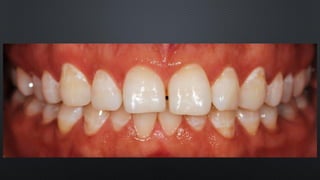

• OCLUSÃO HABITUAL, DETERMINADA PELOS DENTES

RELAÇÃO ENTRE ARCOS

MÁXIMA INTERCUSPIDAÇÃO HABITUAL (MIH)

• OCLUSÃO ONDE SE OBTÉM O MAIOR NÚMERO DE CONTATOS DENTAIS

POSSÍVEIS

• POSIÇÃO DE REABILITAÇÃO EM PACIENTES DENTADOS COM OCLUSÃO

ESTÁVEL

• OCLUSÃO HABITUAL,DETERMINADA PELOS DENTES RELAÇÃO ENTRE ARCOS MÁXIMA INTERCUSPIDAÇÃO HABITUAL (MIH) • OCLUSÃO ONDE SE OBTÉM O MAIOR NÚMERO DE CONTATOS DENTAIS POSSÍVEIS • POSIÇÃO DE REABILITAÇÃO EM PACIENTES DENTADOS COM OCLUSÃO ESTÁVEL